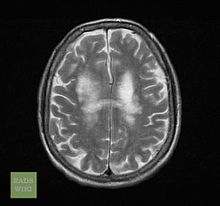

- Enzephalopathie, HIV-bedingt

- Lymphom, primär zerebral

- Progressive multifokale Leukenzephalopathie

- Toxoplasmose, zerebral

Die Diagnose AIDS wird gestellt, wenn bei einem HIV-Positiven bestimmte Infektionen oder bösartige Tumoren, die sogenannten AIDS definierenden Erkrankungen, festgestellt werden. Die Infektionen werden als opportunistische Infektionen bezeichnet. Für das (intakte) Immunsystem eines gesunden Menschen sind sie oft harmlos. Durch das kompromittierte Immunsystem eines HIV-Positiven kann sich der Organismus jedoch nicht ausreichend wehren; es treten die oben genannten Infektionen auf. Als Maß für die Zerstörung des Immunsystems dient die T-Helfer-Zellen-Zahl im Blut eines HIV-Infizierten. Unter der Schwelle von 200–400 / µl Blut ist die Therapie indiziert. Im späten Stadium kann sich eine subkortikale Demenz entwickeln.